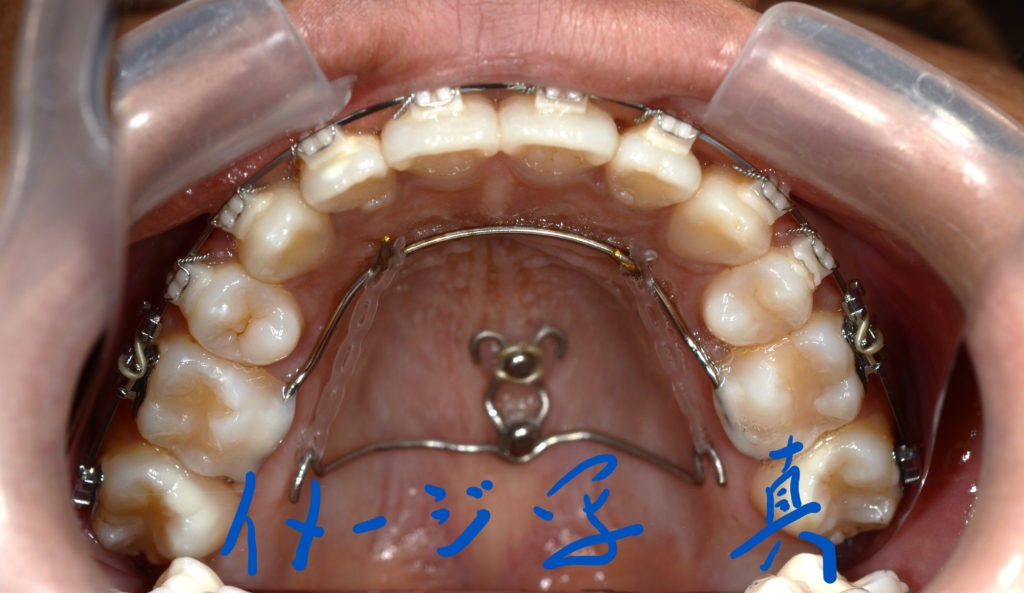

アンカースクリュー

(上顎の口蓋に2本使用)

あらためて、上顎にアンカースクリューを植立しました。

アンカースクリューを用いて矯正力を加えることで、上顎歯列全体を後方へ移動させて、口元の見た目の更なる改善を図ります。

同じことをしている方の写真をイメージ写真としてあげています。

【治療装置】 スタンダードtypeのマルチブラケットシステム、

アンカースクリューを2本

PLAS & パラタルバー